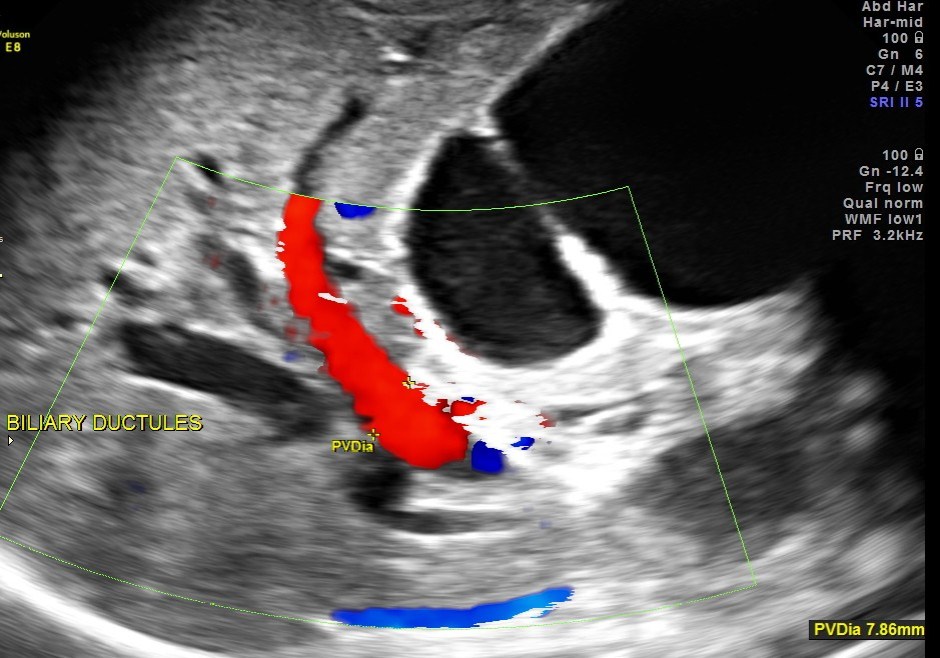

Courvoisier’s law (or Courvoisier syndrome, or Courvoisier’s sign or Courvoisier-Terrier’s sign) states that in the presence of an enlarged gallbladder which is nontender and accompanied with mild jaundice, the cause is unlikely to be gallstones. Usually, the term is used to describe the physical examination finding of the right-upper quadrant of the abdomen. This sign implicated possible malignancy of the gall bladder or pancreas and the swelling is unlikely due to gallstones.

This was a 55 year old man with history of jaundice and upper abdominal pain .